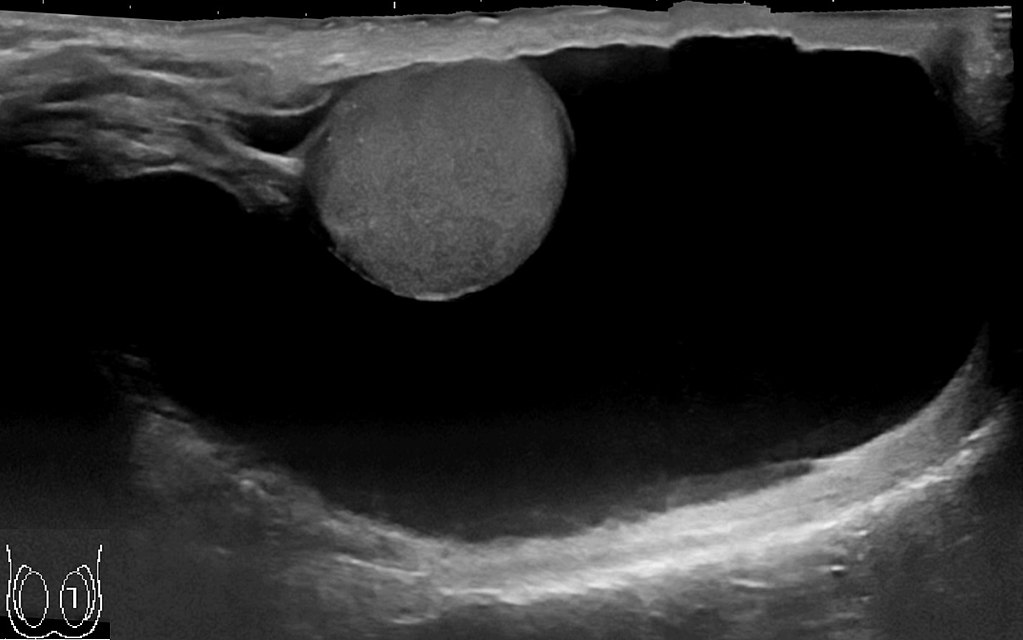

Testicular tumors present as a firm, painless testicular mass which cannot be transilluminated.

Testicular tumors are generally not biopsied because of risk of seeding the scrotum.

Malignant germ cell tumors represent the majority of testicular cancers.

Testicular tumors are removed through radical orchiectomy.

Seminomas (which account for 55 percent of cases) have a great prognosis, late metastasis, and a high radiation treatment response rate.

Large cells with transparent cytoplasm and central nuclei (like spermatogonia) make up the malignant tumor known as a seminoma, which develops as a homogeneous mass without bleeding or necrosis.